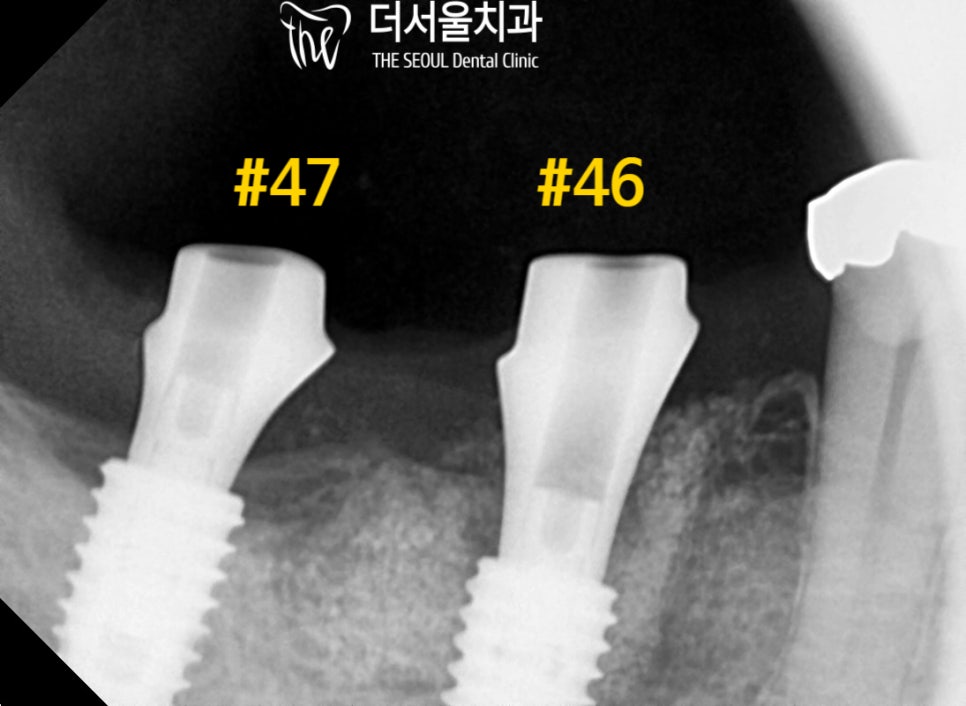

모든 보철이 완성되었습니다.

흔들리던 크라운은 물론이며

염증이 생겨 있던 곳까지

튼튼한 보철로 채워져 있는데요.

정말 자연스럽게 구강 내에

자리를 잡고 있는 크라운들이 확인되었습니다.